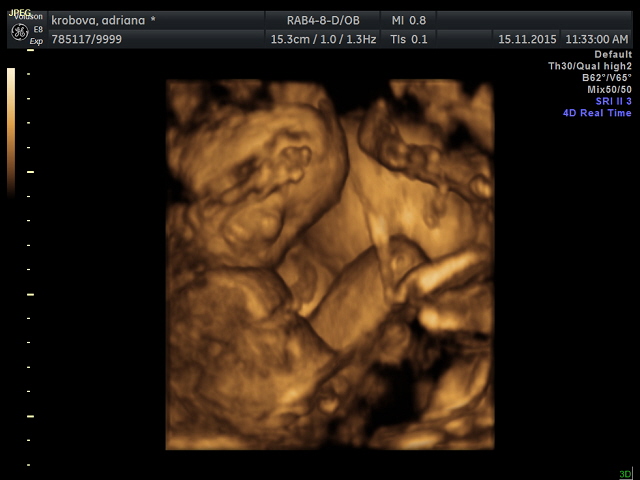

Takže miminko 8 je Matěj schovaný za ručičkou- kde vykukuje jen nosánek, pusinka a trochu stín oka :0) Líp ho Rozárka nenechala "cvaknout" No a třináctka je naše modelka :0))